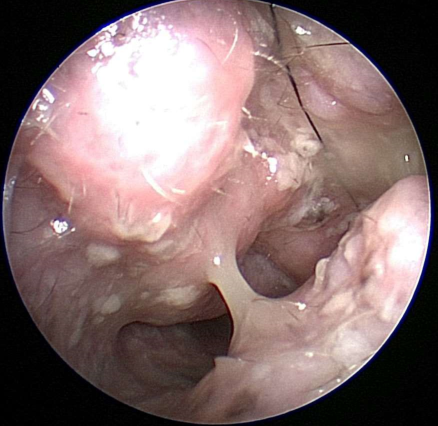

What do you see at the opening of the canal with Pseudomonas infections?

Mucopurulent, sticky material

Swollen, sore, painful